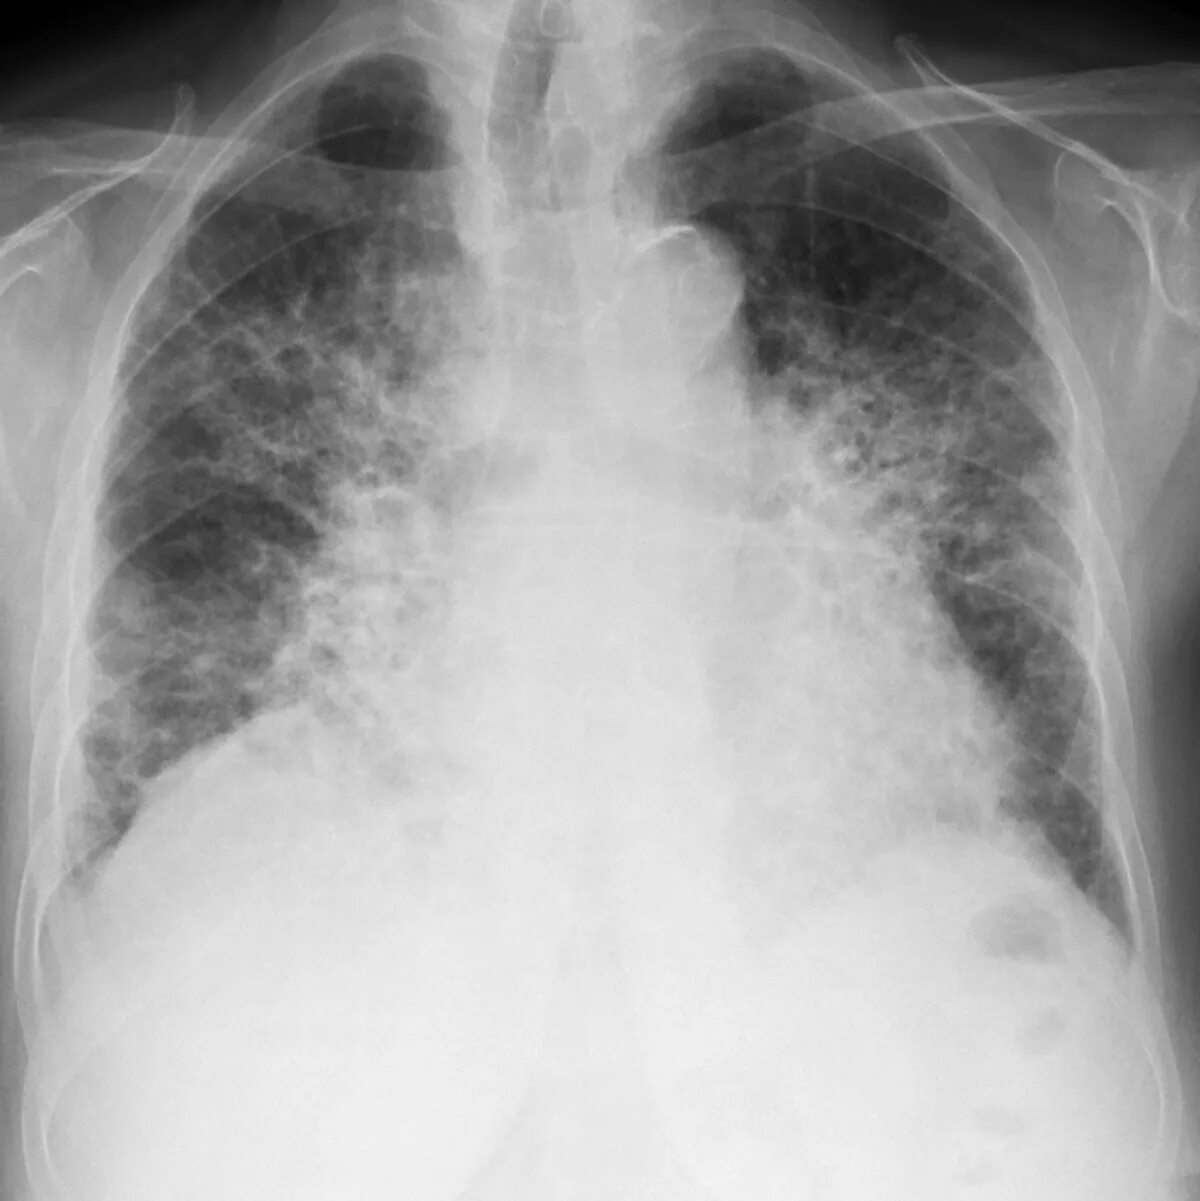

Как лечить пневмофиброз легких у взрослых